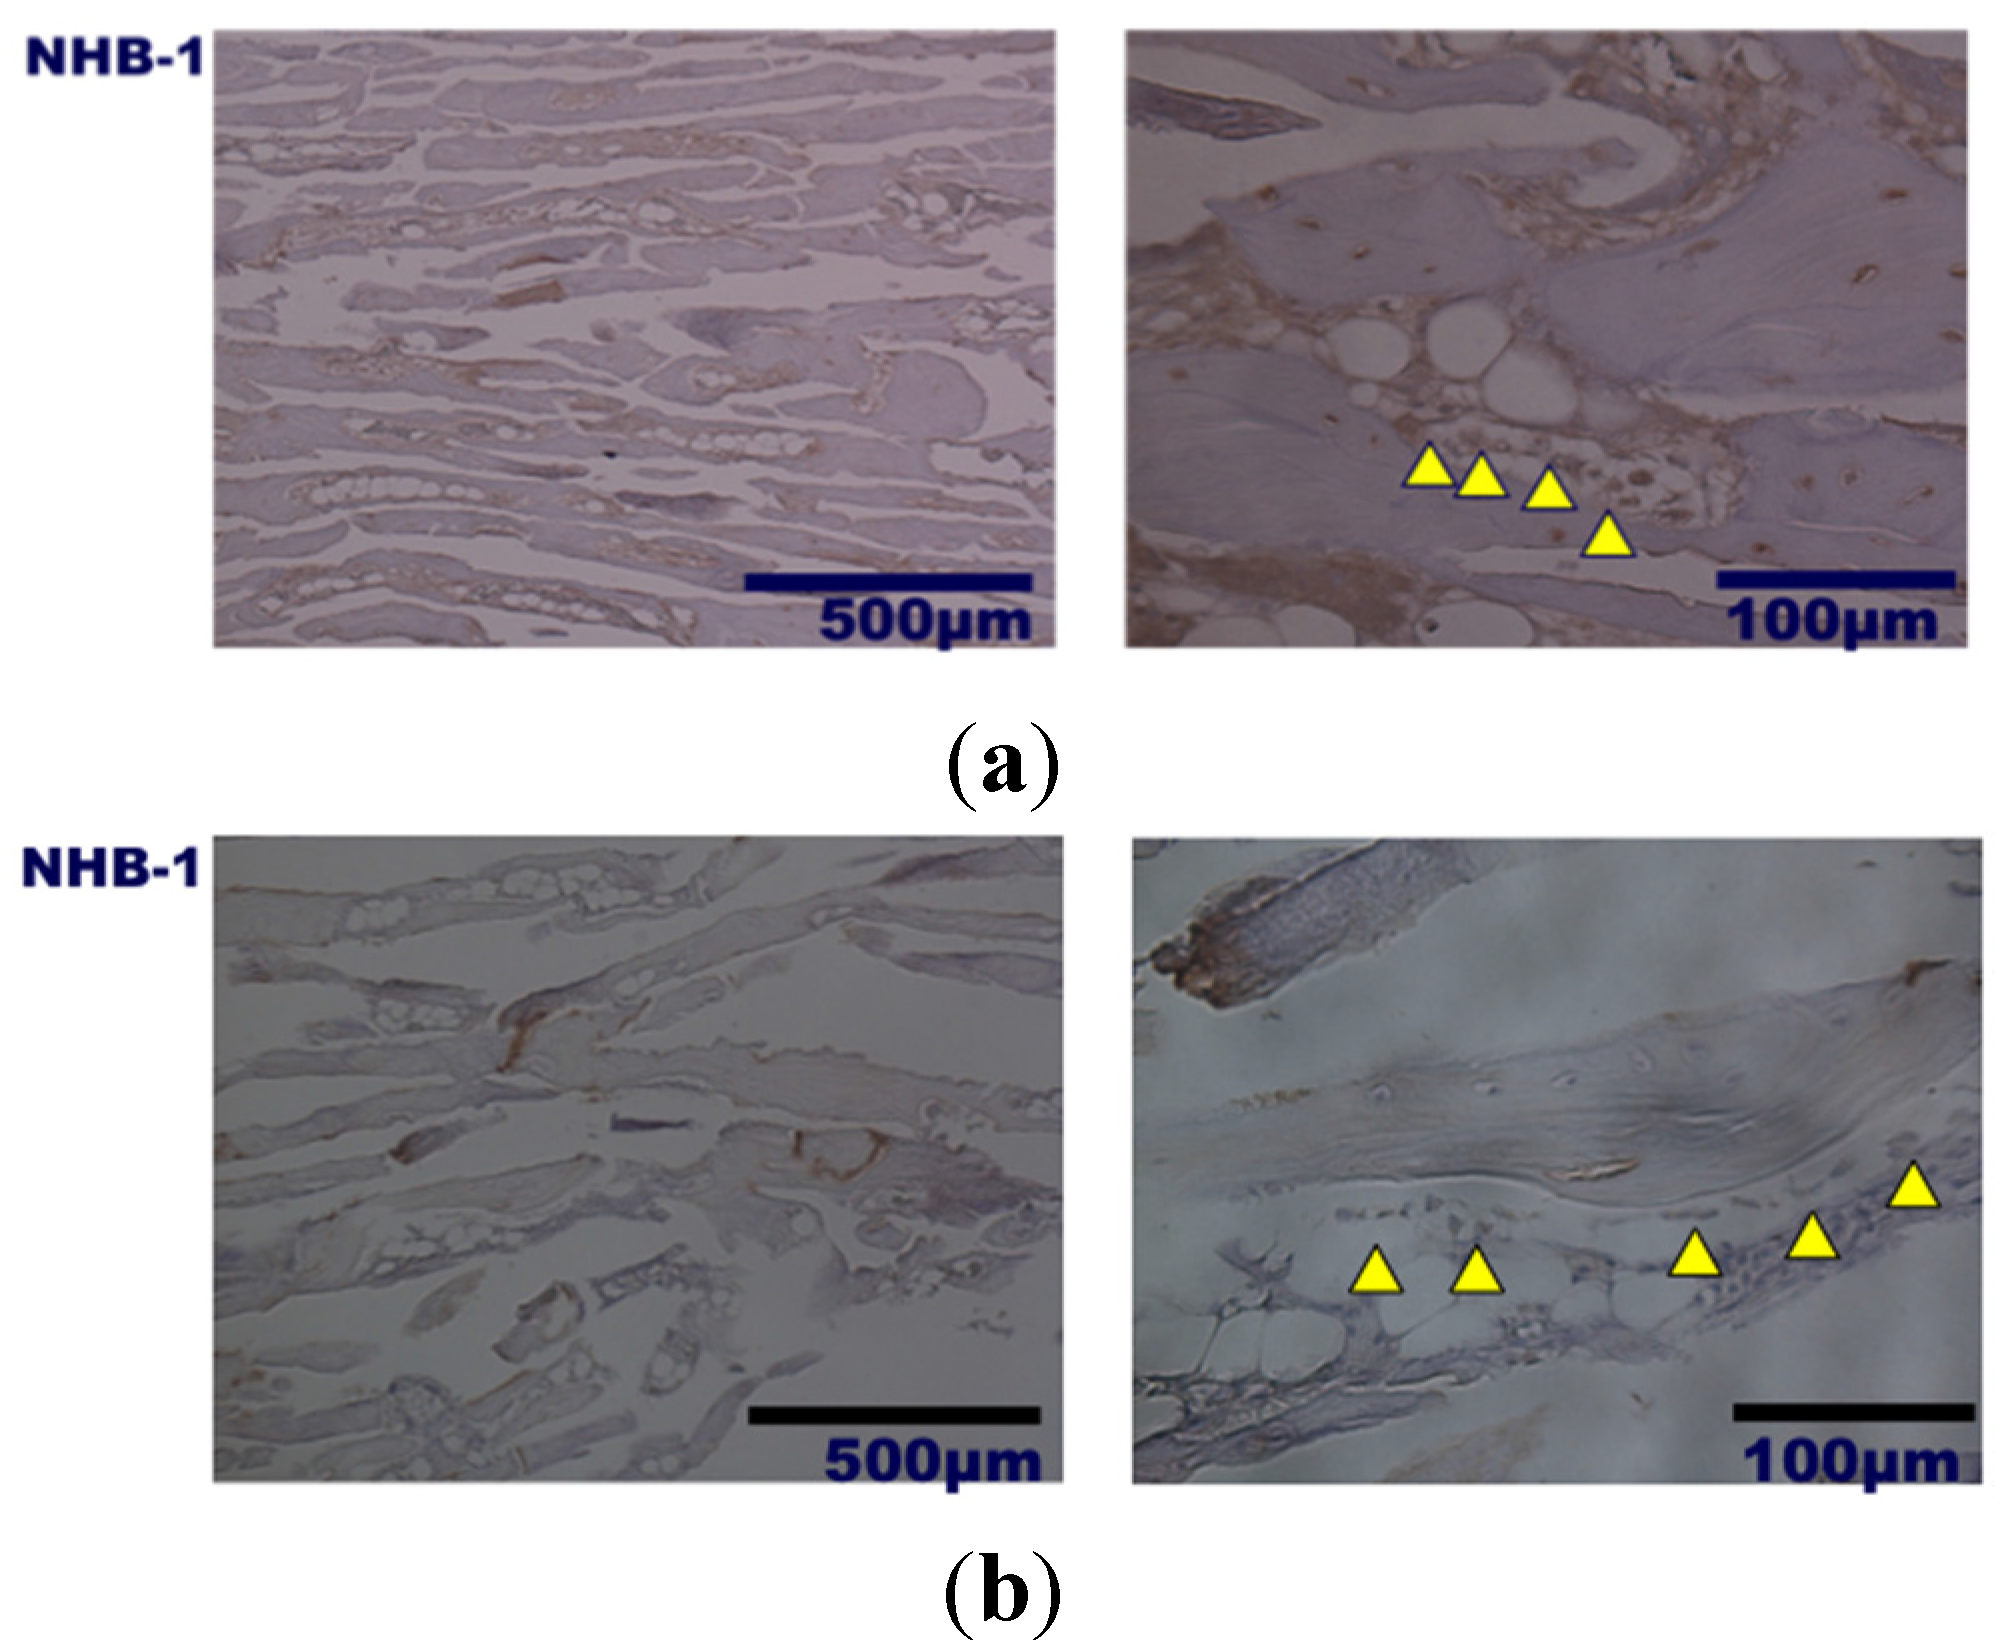

2. Results and Discussion

3.3. Bone Formation in Cortical and Medullary Bone Regions